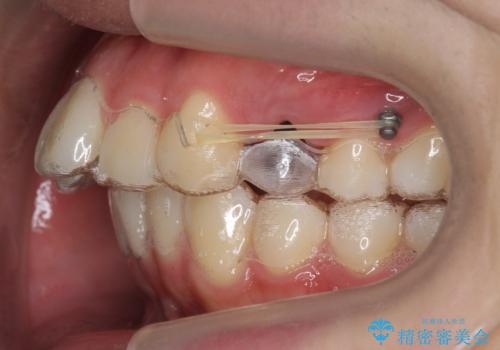

矯正用ミニスクリューを使用しています(インプラント矯正)。

奥歯の歯ならびのずれが大きく、親知らずを抜いてすべて後ろに下げるか、手前の歯を抜いて前歯を下げるかの2択でした。

時間はかかりましたがしっかり前歯を下げて治療しています。